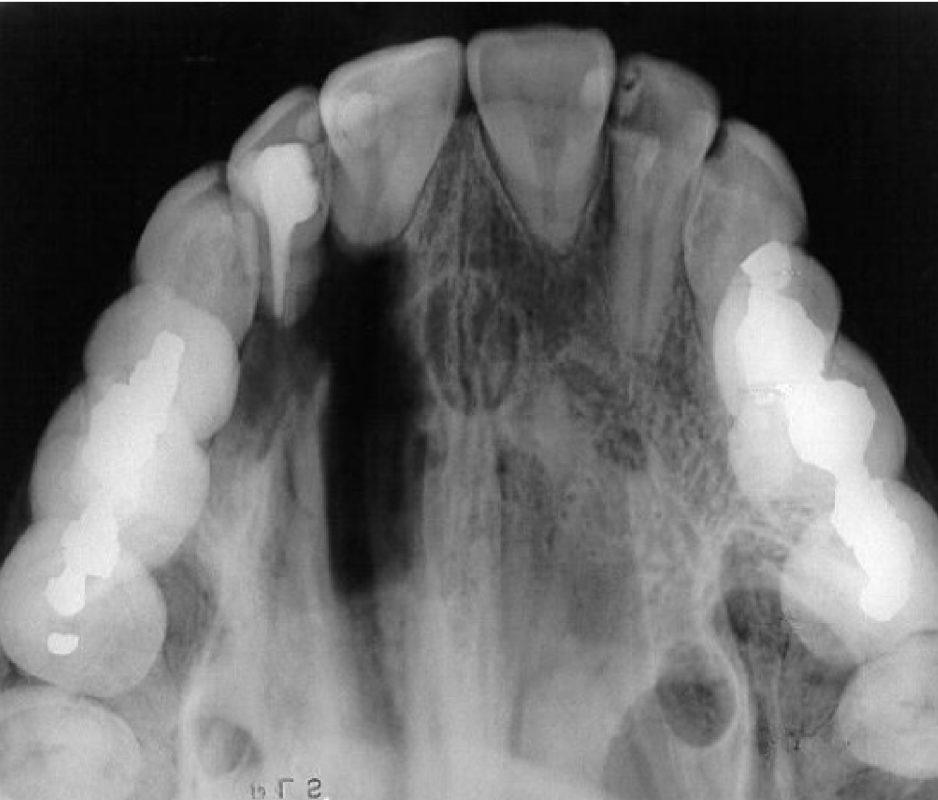

La radiografía de senos paranasales es una técnica de imagen que se utiliza para examinar las cavidades llenas de aire en los huesos que rodean la nariz, conocidas como senos paranasales. Incluyen los senos maxilares, etmoidales, esfenoidales y frontales. Puede ser realizada para diversos propósitos, como:

- Evaluación de la anatomía

- Detección de tumores o quistes

- Evaluación de fracturas